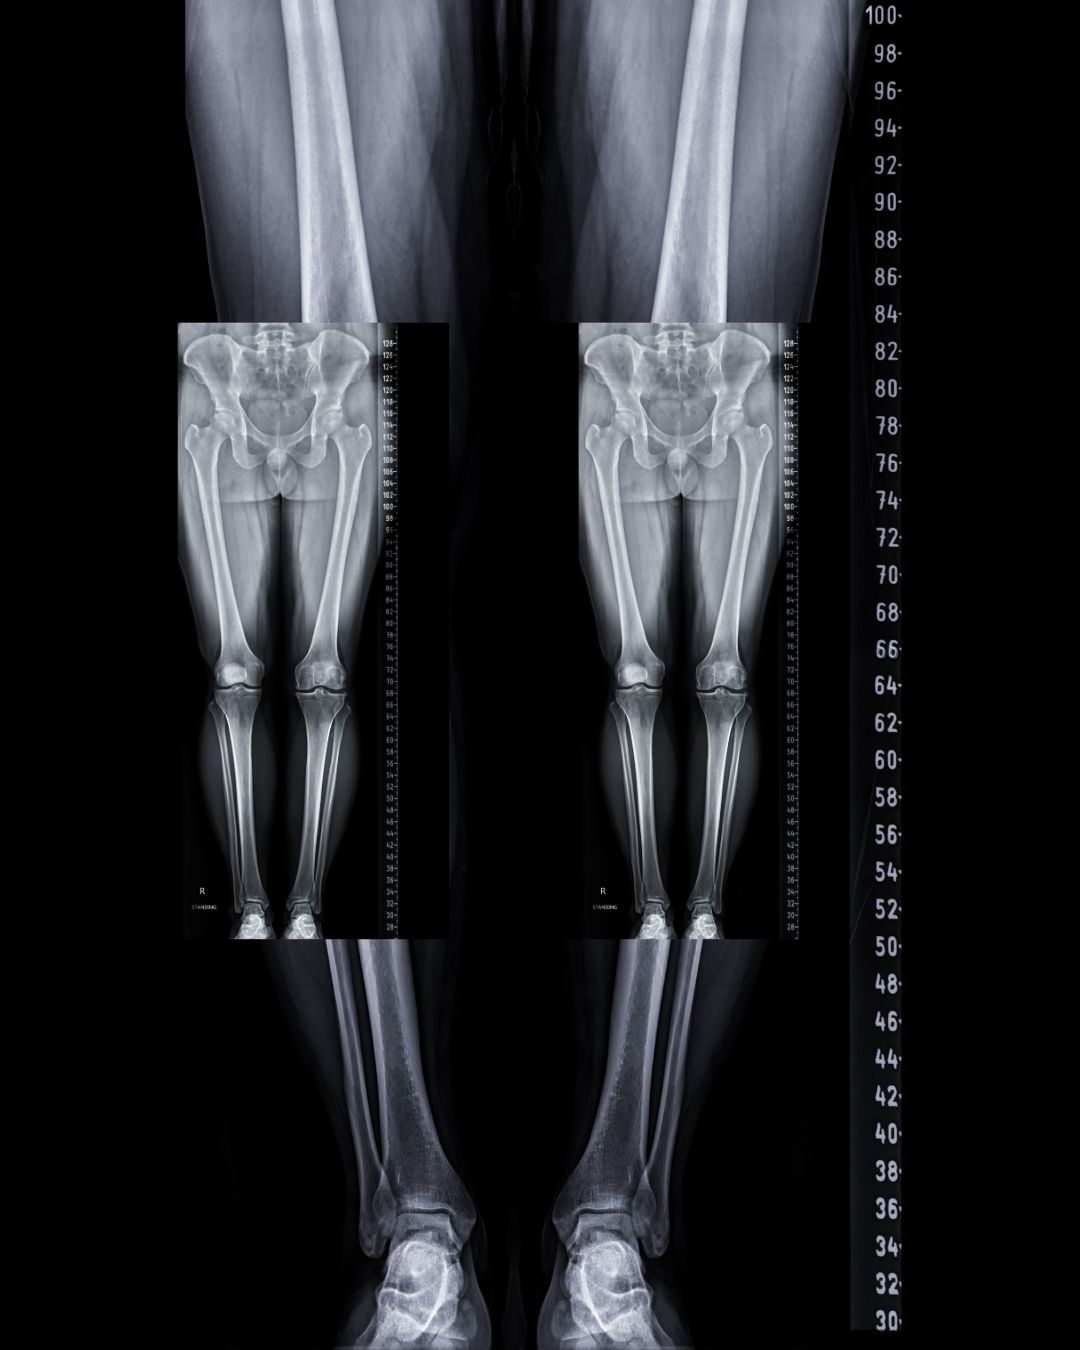

Bacak Uzunluk Grafisi, genellikle ortopedi ve fizik tedavi alanında kullanılan bir görüntüleme ve ölçüm yöntemidir. Amaç, bacaklar arasındaki uzunluk farkını belirlemek, duruş ve yürüyüş problemlerini değerlendirmek veya büyüme çağındaki çocuklarda bacak gelişimini takip etmektir.

Hasta genellikle ayakta durur ve bacak uzunlukları diz, kalça ve ayak bileği referans noktalarından ölçülür. Ölçümler bazen direkt grafi veya röntgen ile desteklenir.

Grafikte bacak uzunluk farkı milimetre veya santimetre cinsinden gösterilir ve hekim bu veriyi tedavi planlamasında kullanır.